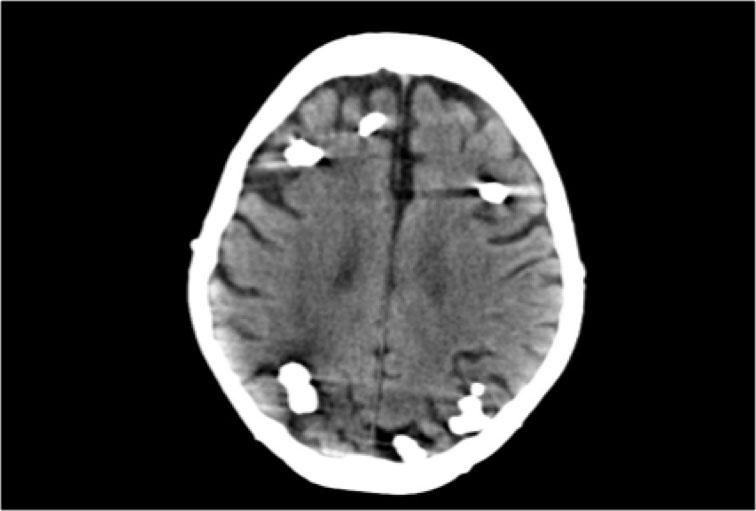

75% trường hợp xuất hiện dưới dạng tổn thương đơn độc, tản phát và 10-30% xuất hiện dưới dạng tổn thương đa ổ.

Cavernoma bao gồm các tiểu thùy có kích thước khác nhau chứa các sản phẩm máu ở nhiều giai đoạn tiến triển khác nhau, tạo nên hình ảnh đặc trưng “bỏng ngô” (popcorn).

Một vành hemosiderin hoàn chỉnh bao quanh tổn thương, ngoại trừ trường hợp có chảy máu gần đây.

CT không tiêm thuốc cản quang có thể cho thấy một nốt tăng tỷ trọng hoặc vôi hóa, nhưng trong 50% trường hợp, cavernoma sẽ không được phát hiện trên CT.

Chuỗi xung T2W và T2* gradient echo cho thấy nhiều cavernoma.

Lưu ý hình ảnh “bỏng ngô” với vành hemosiderin ngoại vi trên chuỗi xung T2W.

Các tổn thương gần như hoàn toàn màu đen trên chuỗi xung gradient echo do xảo ảnh blooming.

Chuỗi xung T2* và hình ảnh trọng số độ nhạy từ (SWI) làm tăng đáng kể độ nhạy của MRI trong việc phát hiện các cavernoma nhỏ.

Năm chấm đen ở bán cầu đại não trái trên chuỗi xung T2* cũng là cavernoma và không thể nhìn thấy trên chuỗi xung T2W.

CT không tiêm thuốc cản quang cho thấy một vôi hóa nhỏ ở nhân thấu kính bên phải.

CT có tiêm thuốc cản quang cho thấy một dị dạng tĩnh mạch dẫn lưu cavernoma vào tĩnh mạch não trong bên phải.

Chuỗi xung T2W mặt phẳng coronal cho thấy dị dạng tĩnh mạch dưới dạng một khoảng trống dòng chảy hình đường cong.